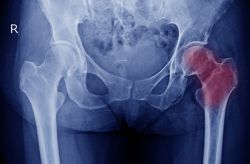

Cách đây một năm, anh C.D.H (Hà Nội) xuất hiện những cơn đau dai dẳng ở vùng khớp háng trái. Theo thời gian, tần suất và mức độ cơn đau tăng dần, làm đảo lộn hoàn toàn cuộc sống cũng như sinh hoạt của anh. Qua thăm khám, bác sĩ kết luận anh bị hoại tử vô mạch chỏm xương đùi (hoại tử chỏm xương đùi) bên trái.

Hoại tử vô mạch hay hoại tử xương là tình trạng mô xương bị chết do không được cung cấp máu. Hoại tử vô mạch gây nên những vết nứt nhỏ trong xương và làm cho xương bị vỡ. Quá trình này thường kéo dài vài tháng đến vài năm.